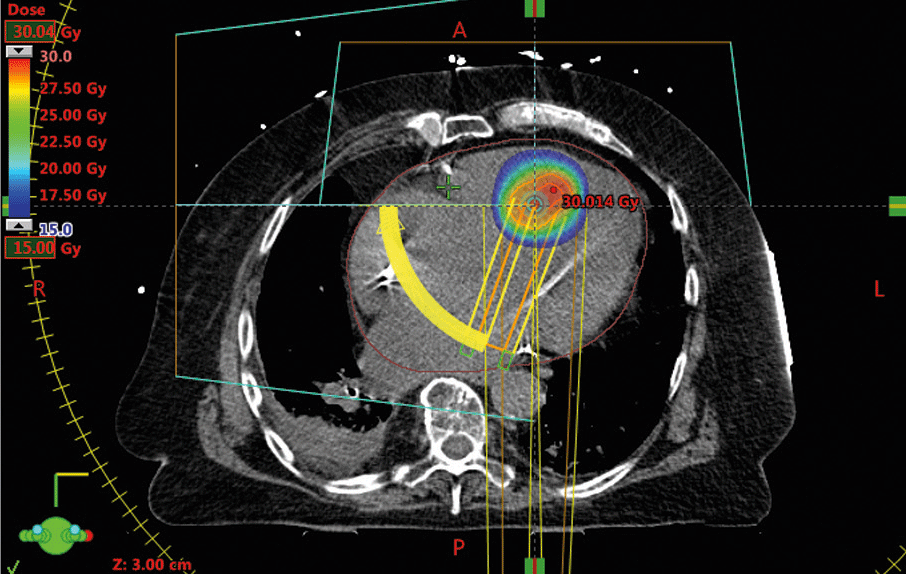

Mapping auf hochauflösendem Niveau (links): Mehr als 10 000 Datenpunkte lieferten ein Bild des linken Ventrikels. So ließ sich das arrhythmogene Areal genau identifizieren und das Zielvolumen für die Bestrahlung berechnen (rechts). Mapping auf hochauflösendem Niveau (links): Mehr als 10 000 Datenpunkte lieferten ein Bild des linken Ventrikels. So ließ sich das arrhythmogene Areal genau identifizieren und das Zielvolumen für die Bestrahlung berechnen (rechts). © Universitätsklinikum Schleswig-Holstein, Campus Kiel

Vor der eigentlichen Bestrahlung machten die Experten die Zielregion im Myokard ausfindig, also den Ort der frühesten elektrischen Aktivität während einer VT. Dazu nutzten sie eines der modernsten verfügbaren Mapping-Systeme. Dieser spezielle Katheter mit 64 Elektroden auf mehreren Lamellen misst die Reizweiterleitung und nimmt über 10 000 Datenpunkte auf. Je mehr Werte es gibt, desto enger lässt sich später das Zielvolumen definieren. Zum Vergleich: Andere Verfahren liefern im besten Fall 150–200 Datenpunkte.

Mapping plus hochauflösendes CT erlaubten die exakte Lokalisation des arrhythmogenen Herdes (s. Abb.). Letztlich wurde ein 2,5 cm³ großes Areal im Septum mit 25 Gy gezielt bestrahlt. Die Radiatio erfolgte atemsynchron und das Prozedere dauerte weniger als 30 Minuten. Seit der Behandlung fühlt sich der Patient laut Prof. Bonnemeier deutlich besser. Strahlenassoziierte Komplikationen traten keine auf. Gelegentlich kommt es noch zu Kammertachykardien, die aber spontan sistieren. „Diese wird er auch weiterhin haben“, erklärt der Kollege. Wichtig ist: Die selbstlimitierenden Arrhythmien spielen klinisch keine Rolle, ein Defi-Schock bleibt aus. Der 79-jährige Mann ist damit der erste Patient in Deutschland und einer der ersten weltweit, bei dem eine therapierefraktäre VT mittels Radiatio erfolgreich behoben wurde. Bereits Ende 2017 publizierte ein US-amerikanisches Team eine Pilotstudie mit fünf Teilnehmern, deren Arrhythmien fast vollständig verschwanden (Reduktion um 99,9 %). Darauf folgte eine prospektive Phase-I/II-Studie mit 19 Patienten und ähnlichen Ergebnissen. Alle Betroffenen, die die Behandlung bislang erhalten haben, litten unter einer terminalen Herzinsuffizienz, meistens auf dem Boden einer ischämischen Kardiomyo­pathie. Herzchirurgische Optionen kamen nicht infrage. Bei diesen Patienten hält der Kieler Kollege die Bestrahlung für einen guten Ansatz. „Und der klappt auch.“ Ob durch die Maßnahme die Überlebensrate steigt, bleibt vorerst offen. Primär handelt es sich um einen palliativen Ansatz, der die Lebensqualität verbessert. „Das ist kein Verfahren, das wir jetzt wie Brot und Butter anbieten möchten“, betont Prof. Bonnemeier. Jüngeren mit bekannten VT und gelegentlichen Defi-Schocks solle man keine falschen Hoffnungen machen. Erst wenn Herzinsuffiziente unter maximaler Medikation immer wieder traumatisierende Schockereignisse erleben, könnte die Bestrahlung womöglich eine Option werden. Unter dem Gesichtspunkt der Palliation rückt die potenzielle kardiale Spättoxizität der Radiotherapie in den Hintergrund.

Mapping auf hochauflösendem Niveau: Mehr als 10 000 Datenpunkte lieferten ein Bild des linken Ventrikels. Mapping auf hochauflösendem Niveau: Mehr als 10 000 Datenpunkte lieferten ein Bild des linken Ventrikels. © Universitätsklinikum Schleswig-Holstein, Campus Kiel

So ließ sich das arrhythmogene Areal genau identifizieren und das Zielvolumen für die Bestrahlung berechnen. So ließ sich das arrhythmogene Areal genau identifizieren und das Zielvolumen für die Bestrahlung berechnen. © Universitätsklinikum Schleswig-Holstein, Campus Kiel